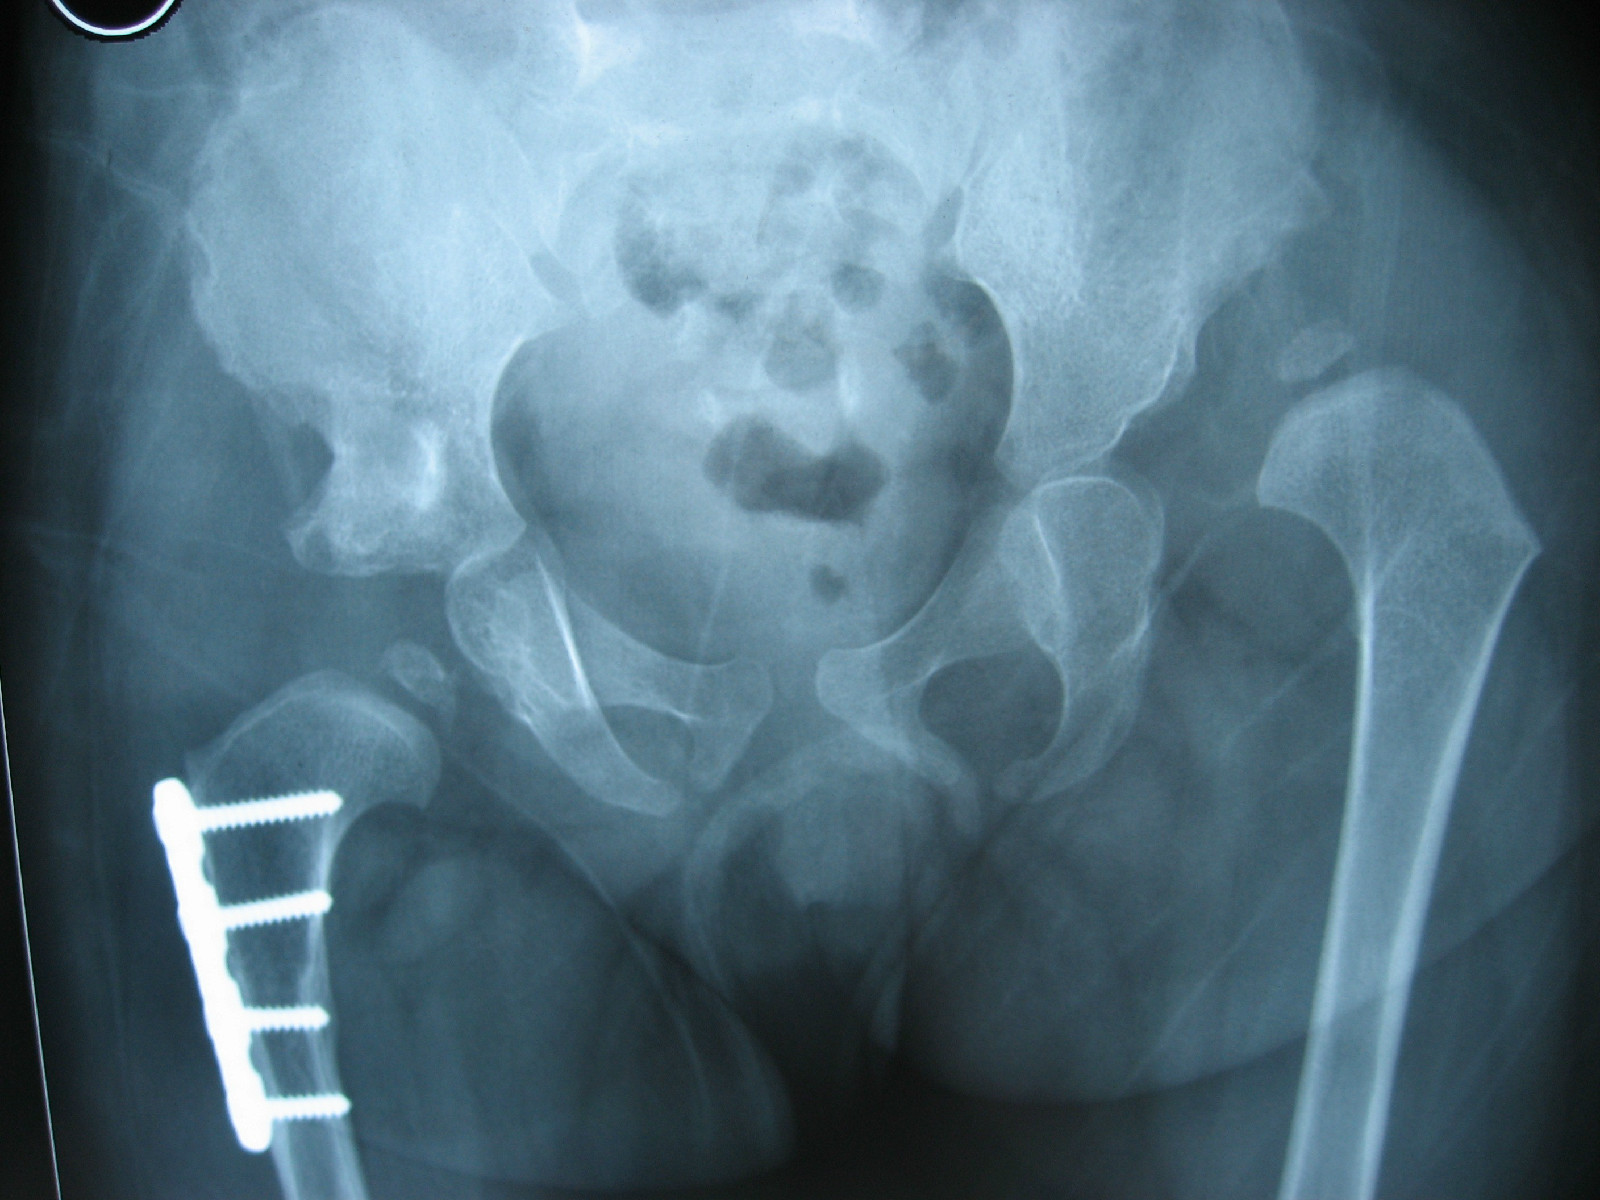

髋关节中心脱位伴髋臼骨折一例柏乡县中心医院骨科

即时求助左髋关节脱位并髋臼骨折目前治疗方案是否需要手术昨天术后